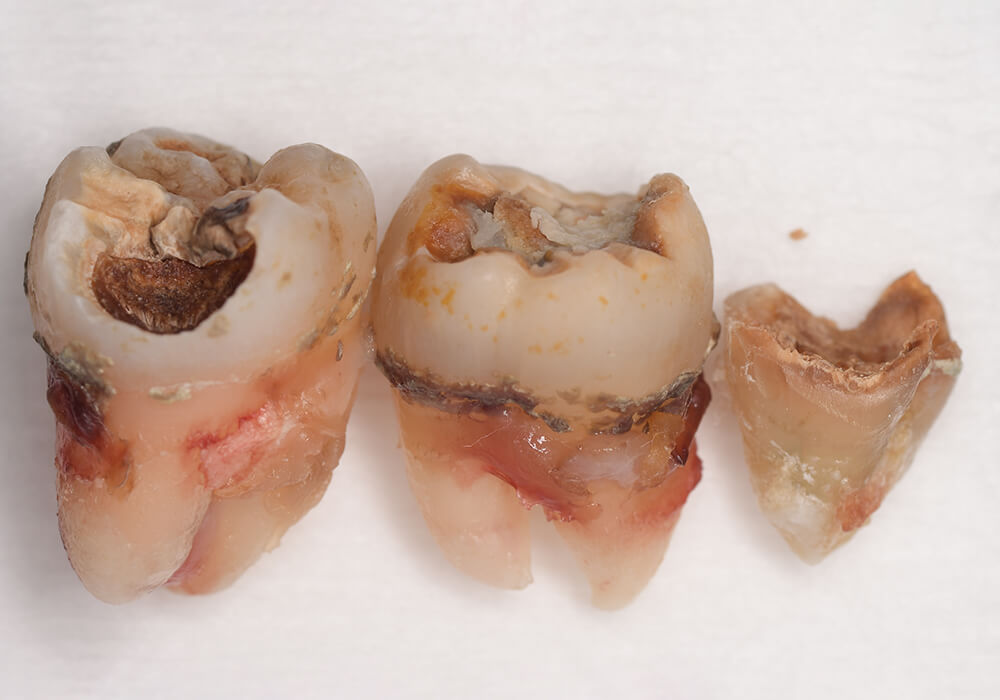

CASE 13

| 年齢・性別 | 32歳・男性 |

| 主訴 | 左上下の奥歯が痛い |

| 抜歯期間 | 60分 |

| 抜歯費用 | 約6,000円 別途CT撮影で3,000円 (2022年8月現在) |

| 抜歯内容 | 左上下の親知らず、左下7抜歯 |

| 治療方針 |

初診時は左上下の痛みでご来院されました。全体的に歯石を除去した後、主訴の解決のために虫歯が進行している左上下の親知らずと左下7の抜歯を行いました。 歯石除去と抜歯を行った後は、痛みが引いてきて口腔内の環境が変わったことに喜んでくれました。 今後は歯ぐきの状態を良くしながら、虫歯や欠損部の治療を行っていきます。 |